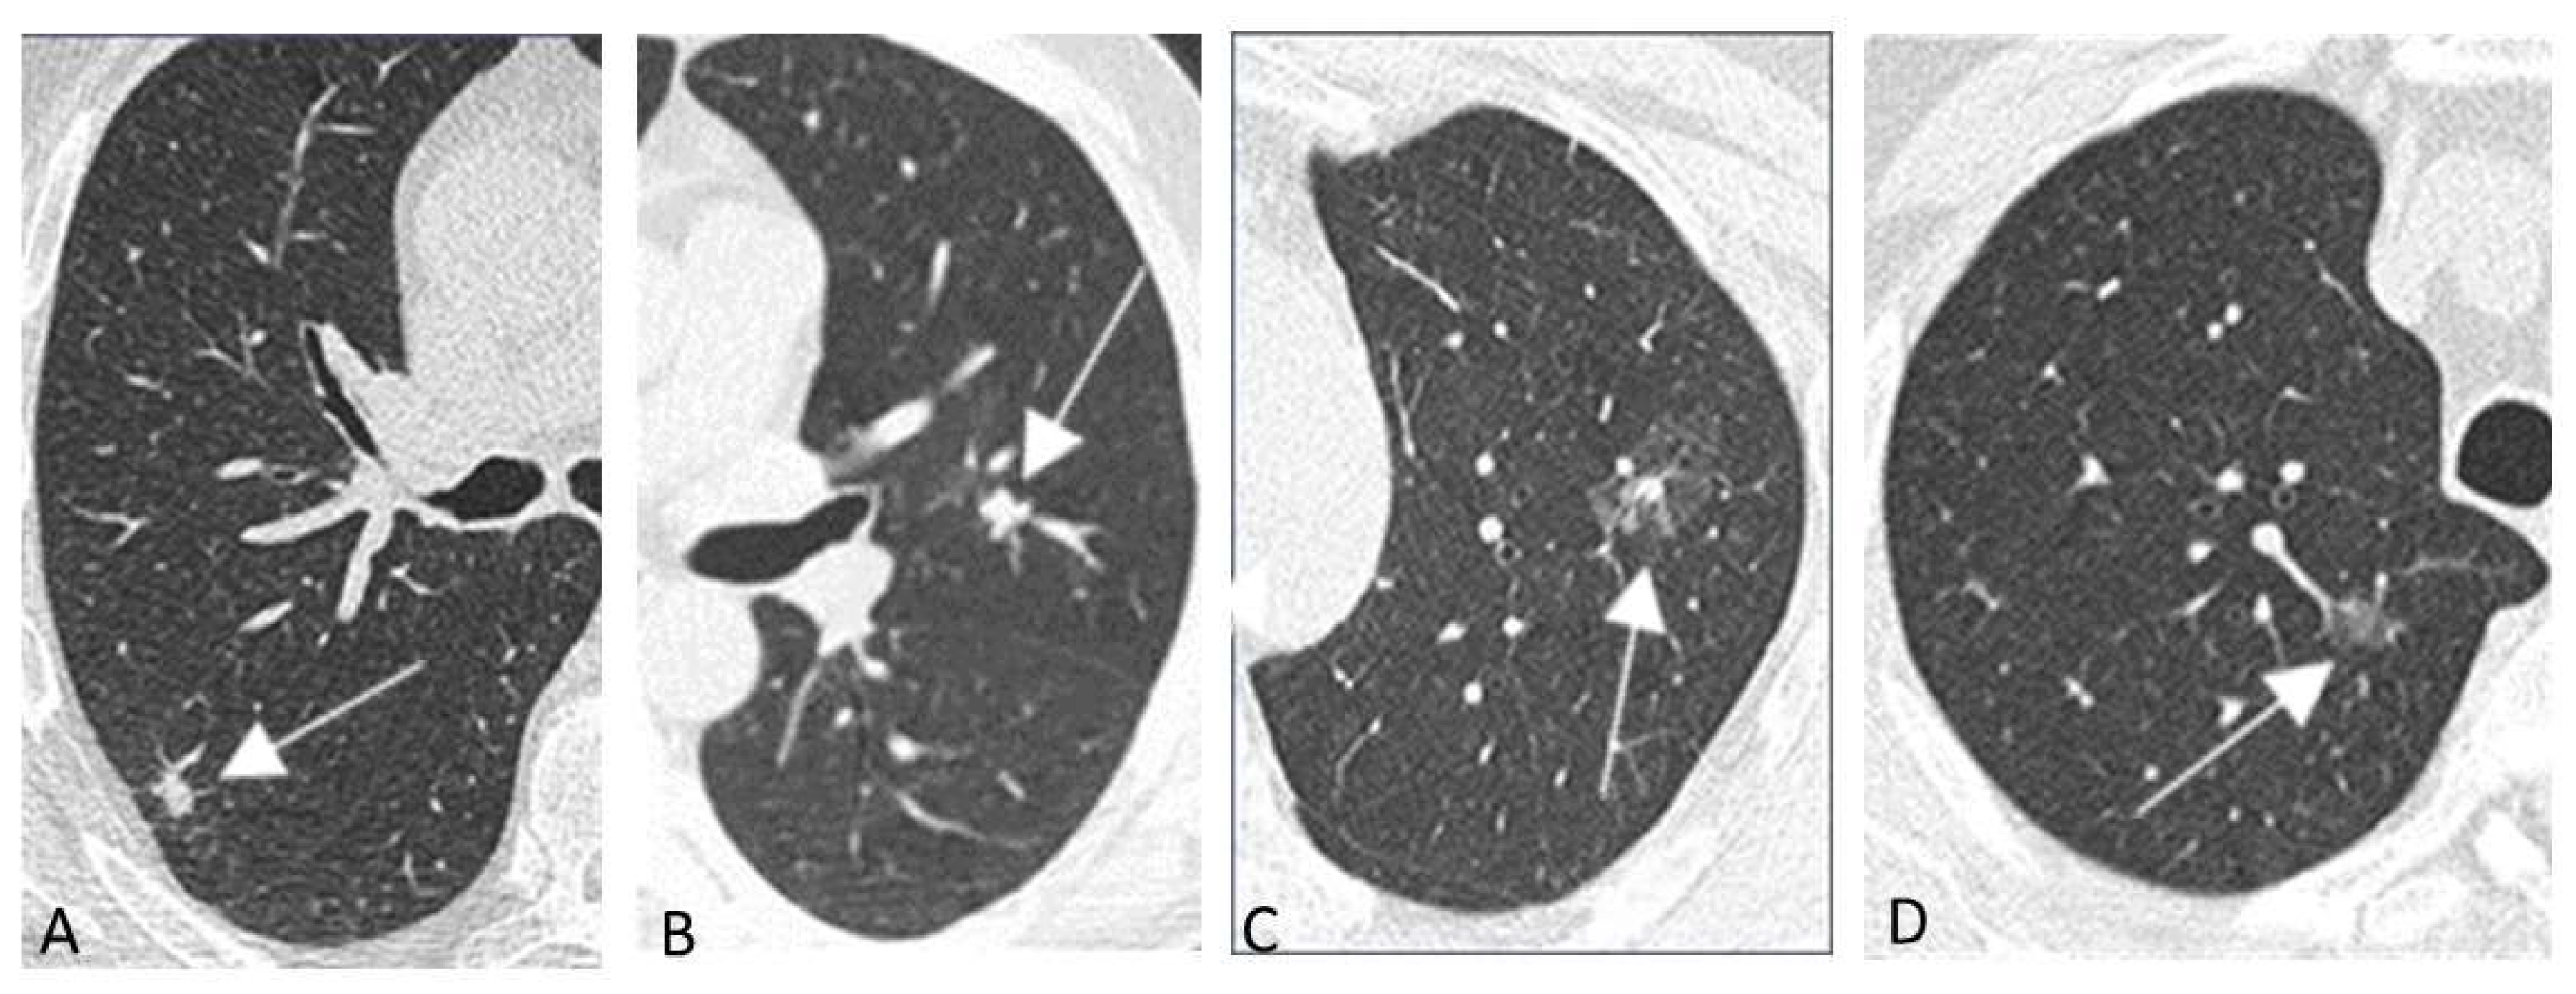

- Mascalchi, M.; Picozzi, G.; Falchini, M.; Vella, A.; Diciotti, S.; Carrozzi, L.; Pegna, A.L.; Falaschi, F. Initial LDCT appearance of incident lung cancers in the ITALUNG trial. Eur. J. Radiol. 2014, 83, 2080–2086. [Google Scholar] [CrossRef]

- Mascalchi, M.; Attinà, D.; Bertelli, E.; Falchini, M.; Vella, A.; Pegna, A.L.; Ambrosini, V.; Zompatori, M. Lung cancer associated with cystic airspaces. J. Comput. Assist. Tomogr. 2015, 39, 102–108. [Google Scholar] [CrossRef] [PubMed]